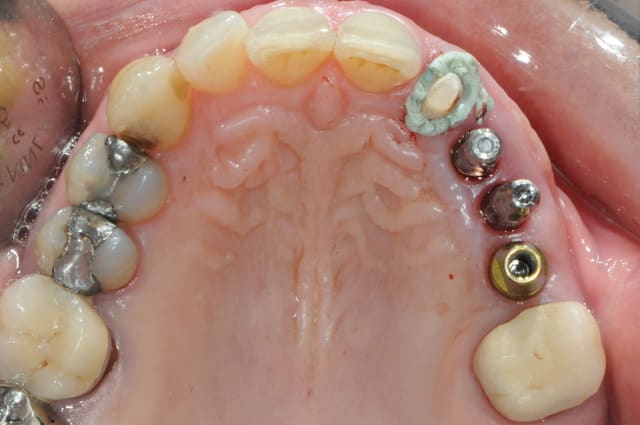

Pour ton anniv pluton je mets un cas identique.

j'ai 6 mois d'avance sur toi dudule

un cas dont j'avais discuté ailleurs avec amibien qui m'avait reproché de ne pas avoir fait la pose en même temps en juin dernier

la pose est de jeudi dernier mon apn est en panne, photo avec le portable, desolé pour le sang mais quand cela saigne il n'y a pas d'échec

il se trouve que j'aimerais utiliser ces photos car c'est le nouveau systeme d'implants, et je n'ai encore pas d'autres cas de fracture en cours

enfin si mais pas aussi belle

j'ai donc agrandi la zone est ce qu'un pro de la photo peut faire mieux?

pour dudule, je ne fais pratiquement jamais de décharge en distal

pour pluton, je viens de poser les implants le cas n'est pas fini